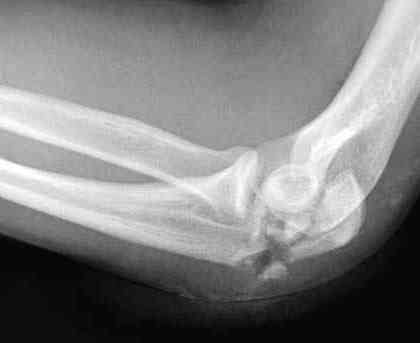

Здесь выставлены несколько случаев и варианты фиксации локтевого отростка, некоторые в комбинации с другими переломами.

1 вариант применен ACUMED локинг пластина

2 вариант

перелом локтевого отростка с переломом головки лучевой кости (использованы 2 мм шурупы)

3 вариант

перелом с capitelum humerus и проксимальной трети улна